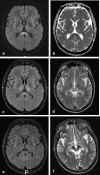

Background and purpose: The splenium of the corpus callosum is the most posterior part of the corpus callosum. Its embryological development, anatomy, vascularization, function, imaging of pathology, possible pathophysiological mechanisms by which pathology may develop and the clinical consequences are discussed.

Methods: A literature-based description is provided on development, anatomy and function. MR and CT images are used to demonstrate pathology. The majority of pathology, known to affect the splenium, and the clinical effects are described in three subsections: (A) limited to the splenium, with elaboration on pathophysiology of reversible splenial lesions, (B) pathology in the cerebral white matter extending into or deriving from the splenium, with special emphasis on tumors, and (C) splenial involvement in generalized conditions affecting the entire brain, with a hypothesis for pathophysiological mechanisms for the different diseases.

Results: The development of the splenium is preceded by the formation of the hippocampal commissure. It is bordered by the falx and the tentorium and is perfused by the anterior and posterior circulation. It contains different caliber axonal fibers and the most compact area of callosal glial cells. These findings may explain the affinity of specific forms of pathology for this region. The fibers interconnect the temporal and occipital regions of both hemispheres reciprocally and are important in language, visuospatial information transfer and behavior. Acquired pathology may lead to changes in consciousness.